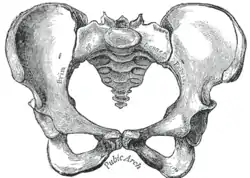

Diameters of superior aperture of lesser pelvis—female Female pelvis

Female pelvis